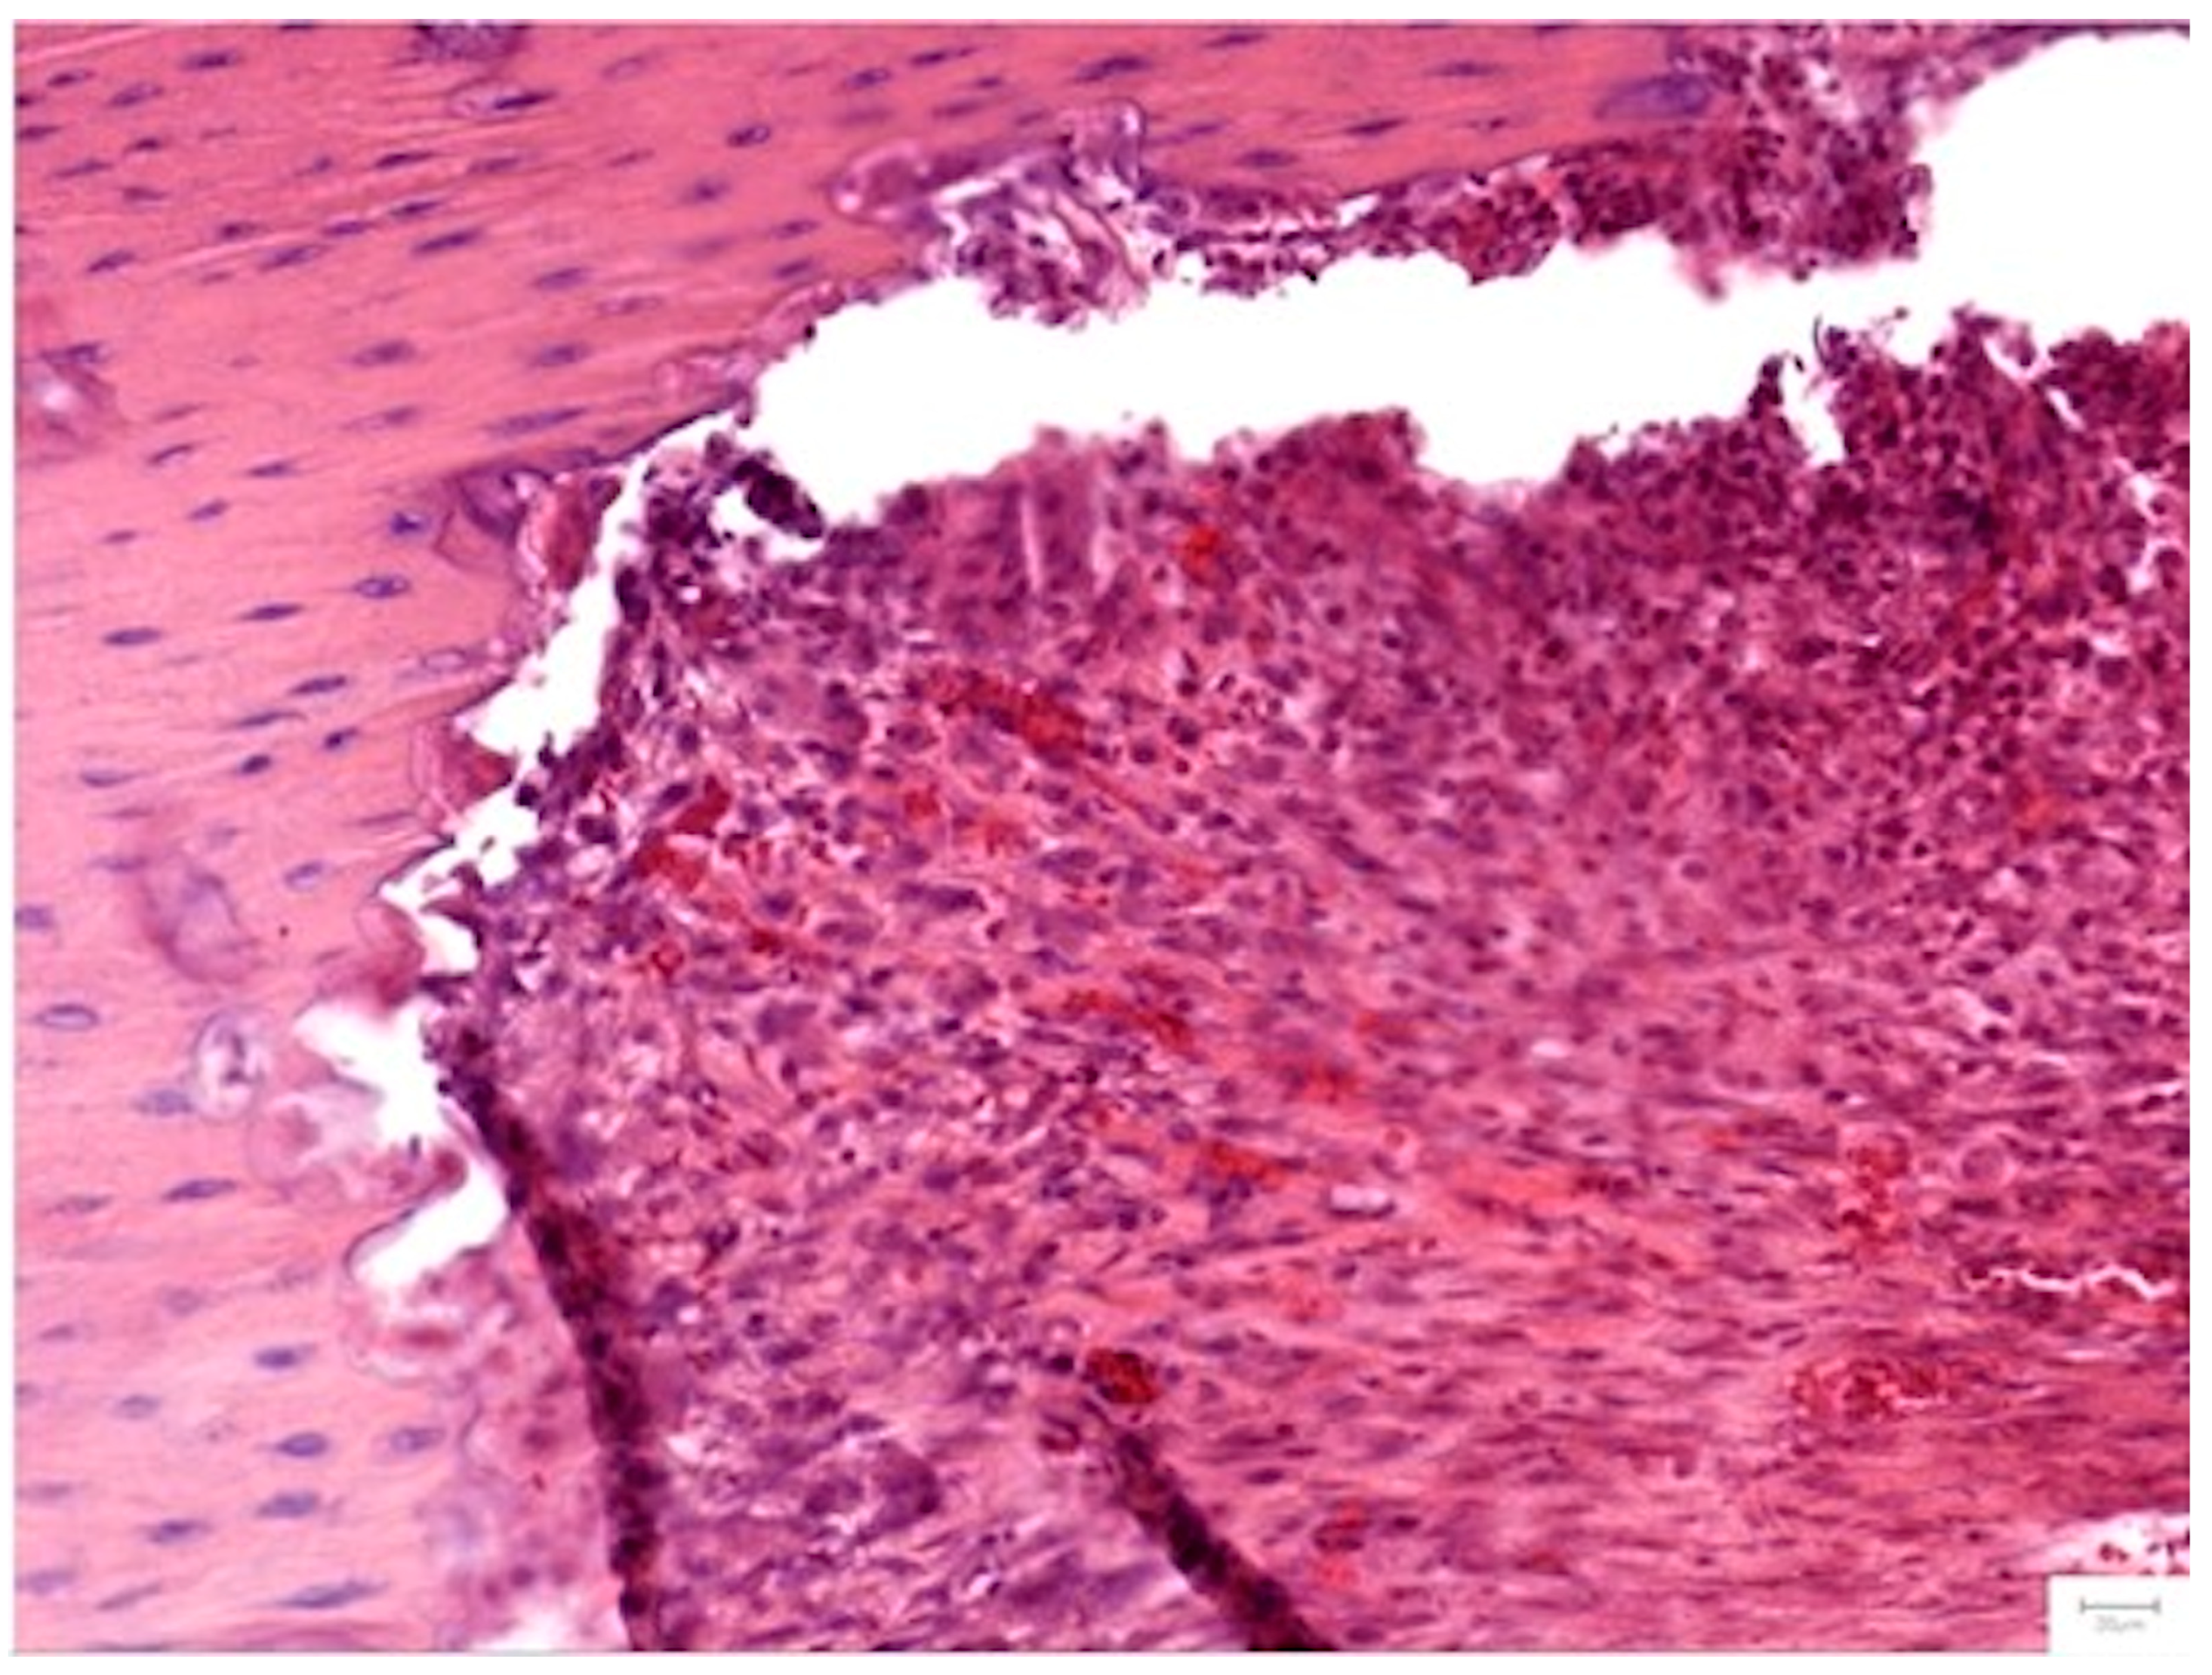

3.3.4. Histopathological Analysis

Local Bone Architecture and Mineralization

Defect Bridging and Healing Patterns

Cellular Response and Vascularization

Graft Integration and Safety